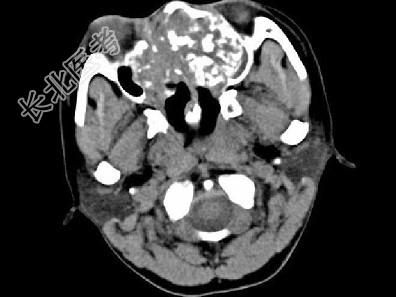

- 单项选择题男,26岁, 进行性鼻腔阻塞、流涕来院就诊,近两年持续性头痛、头晕, 筛窦区病变影像检查如图,最可能的诊断是 ( )